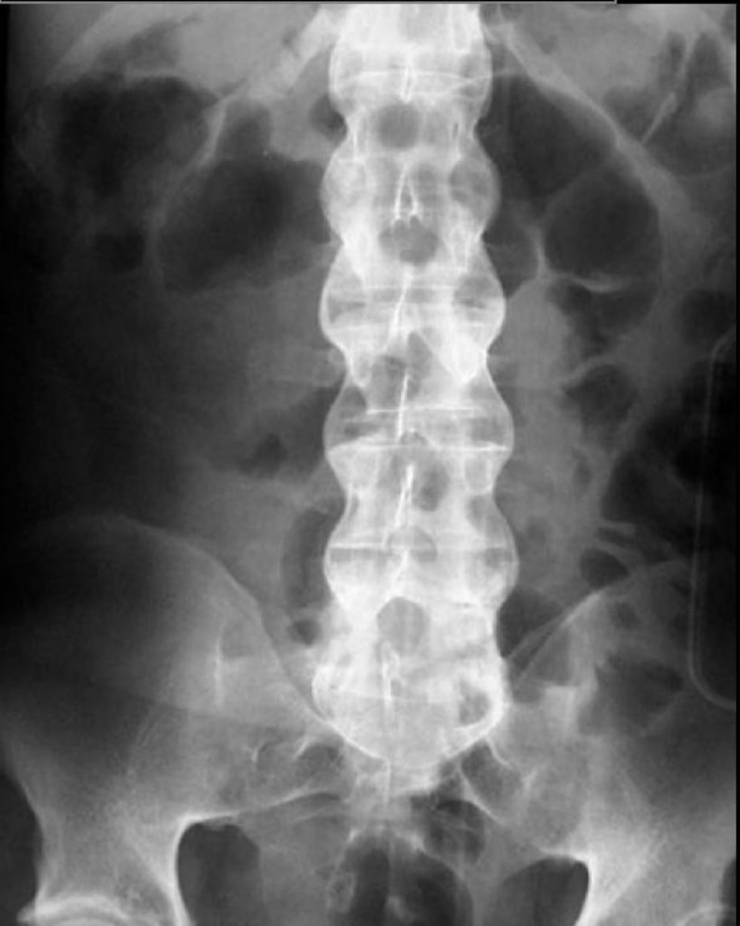

Gece ağrıları içinde en önemli olanların kanser ağrıları olduğunu fakat bu ağrıların nadir olup ileri yaşlarda rastlandığını aktaran Bahadır, "Daha sık rastladığımız gece ağrısı genellikle genç ve orta yaşlarda görülen, sabaha doğru artan ağrılardır. Eğer bu ağrıya birde sabah tutukluğu ekleniyorsa iltihaplı omurga romatizması yani bilinen adıyla ankilozan spondilit hastalığı olma şansı çok yüksek demektir. Ankilozan Spondilit genelde omurgayı bazen omurgaya ek olarak kalça ve diz gibi büyük eklemleri tutan sakatlayıcı bir hastalıktır. Yıllar içinde tüm omurga kemiklerini birbirine yapıştırıp hastayı öne doğru iki büklüm eğer. En önemli özelliği genelde çok sinsi ilerlemesidir. Ağrı ve hareket kısıtlılığı çok yavaş ilerlediğinden kişiler bunu pek önemsemez. Bu sinsi ilerleme yüzünden ilk ağrı şikayetlerinin başlamasından sonra ortalama tanı konma süresi dört beş yılı bulmaktadır. Bu nedenle Ankilozan Spondilit hastalığının en önemli ve erken bulgusu olan gece omurga ağrısı olanlar, hele hele bu ağrıyla beraber sabah tutukluğu şikayeti de olan hastalar çok geç olmadan doktora başvurmalıdır. Yalnız burada bahsettiğimiz sabah tutukluğu herkeste olabilen birkaç dakikalık sabah hamlığı değildir. En az 30 dakika (bazen bir iki saat olabilir) omurga hareketlerini istense de tam yapılamaması ve omurgasının etrafında aşırı bir sertlik hissedilmesi halidir. Genelde birkaç saat içinde bazen öğlene doğru bu sertlik gider ve hasta normal hareket etmeye başlar. Ertesi sabah aynı senaryo tekrarlanır. Bu nedenle bel-sırt bölgesinde sabah tutukluğu uzun süren kişiler en kısa zamanda doktora başvurmalıdır" diye konuştu.

Ankilozan spondilit hastalığının tedavisinde tıbbın artık 15 yıl öncesinde olduğu gibi çaresiz olmadığına dikkat çeken Bahadır, "Yeni çıkan biyolojik tedaviler ile son 10 yılda hastalığın tedavisinde büyük ilerlemeler kaydedildi. Bu hastaların en büyük sorunu olan ve omurga hareketine izin vermeyen dirençli ağrılar artık bu ilaçlar ile kontrol altına alınabilmektedir. Ankilozan spondilitte omurga hareketlerinin kısıtlanmasını önleyen en önemli tedavi ilaç değil egzersizdir. İlaçlar ile ağrı düzeltildikten sonra hastaların düzenli egzersiz yapması ile omurganın eğilmesi engellenebilmektedir. Ama asıl problem hastalığın tanısını erken koymaktır ve omurga kemikleştikten sonra ne ilaç ne egzersiz bunu düzeltemez. Bu nedenle geceleri bel-sırt ağrıları ve sabah tutukluğuna dikkat diyoruz" şeklinde konuştu.